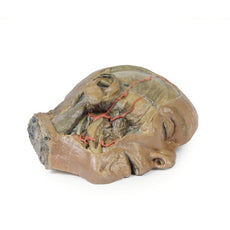

In the preserved midsagittal section there is preservation of the endocranial

contents, the nasal and oral cavities, and the pharynx to the level of the

laryngeal cartilages. The nasal cavity is preserved nearly intact, except for a

small window excised into the middle nasal concha to expose the ethmoid

air cells. A very large sphenoid sinus exists in the individual just superior

to the torus of the auditory tube in the nasopharynx. The oral cavity and

laryngopharynx are undissected, with the larynx only preserve just distal to the

level of the arytenoid cartilages and not including a clear set of vocal folds.

Within the endocranial cavity, the sectioned brain is slightly off the midagittal

plane, such that neither the superior sagittal sinus nor the third ventricle are

clearly defined - but the lateral ventricle is open and part of the fourth ventricle

is preserved between the pons and cerebellum. The gyri and sulci of the

cerebrum are not well separated, but the cingulate gyrus and corpus callosum

can be separated. Cross-sectioned views of the optic tract, pituitary gland,

superior and inferior colliculi, superior cerebellar peduncle, and transition

between the medulla oblongata and spinal cord are all visible. The tentorium

cerebelli and confluence/transverse sinus is positioned between the

cerebellar hemisphere and occipital lobe. Small portions of the posterior

inferior cerebellar artery, vertebral arteries, basilar artery, and posterior

cerebral and anterior cerebral arteries are visible in section.